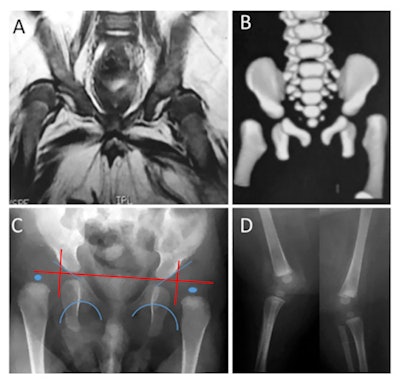

A: MRI shows bilateral dislocation of hips, epiphyseal core (small arrow), and dysplastic acetabulum (large arrow). B: 3D CT shows bilateral dislocation of hips. C: Anteroposterior radiographs show features compatible with dislocation of hips -- interruption of Shenton's arc, epiphysis hypoplastic proximal femoral acetabular index of 35°, and right and left proximal femoral epiphysis located laterally on side and bottom quadrant ombredanne. D: Radiograph shows subluxation of knee (arrows).The seven children underwent neurological and orthopedic examinations along with several other investigations: radiography, brain CT, or brain MRI without contrast, high-definition ultrasound of the joints (with specific attention to cartilage, synovia, pericapsular structures, and muscular tissue around joints), nerve conduction studies, and needle electromyography. If calcifications were present on brain imaging (CT or MRI), the researchers considered the possibility of congenital infections. Four children underwent MRI of the spine. MRI was not possible in two children as they were receiving mechanical ventilation on an intensive unit care.